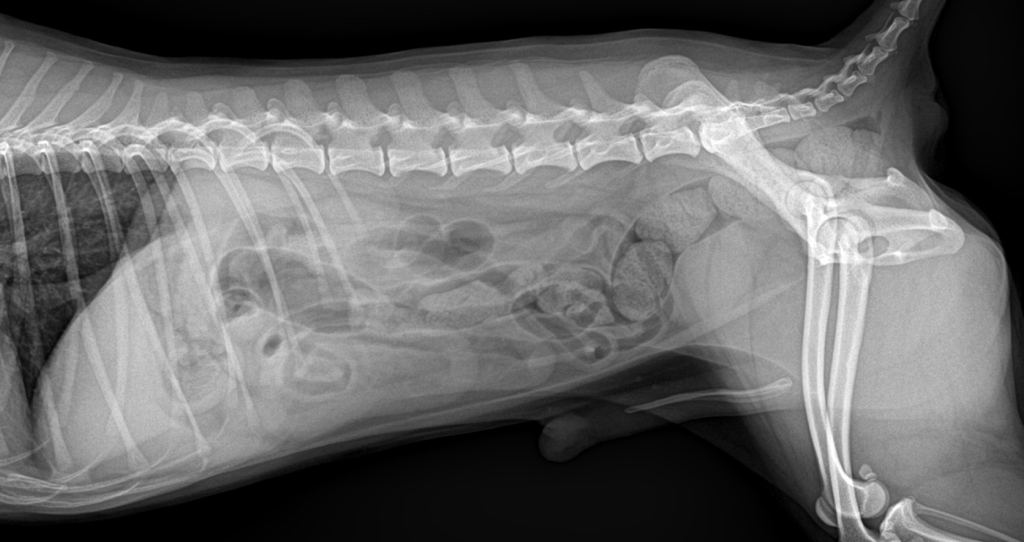

엑스레이상으로 목/허리디스크 확인이 가능한가요?

강아지가 특정부위가 아파서 엑스레이를 찍어봤는데 그렇게 심하지 않으면 엑스레이로는 알수가 없다고 하더라구요 ㅠㅠ.. 보실때 혹시 목이나 허리에 디스크는 보이지 않으신가요😭

디스크를 진단하는 golden standard 검사는 MRI, 검사입니다.

엑스레이는 척추의 골절이타 탈구, 융해성 병변 등 디스크 질환을 유발할 수 있는 몇몇 원인에 대한 감별 평가만 가능한 수준이라고 보아야 하지요.

때문에 엑스레이로는 디스크 여부를 평가해서는 안됩니다.